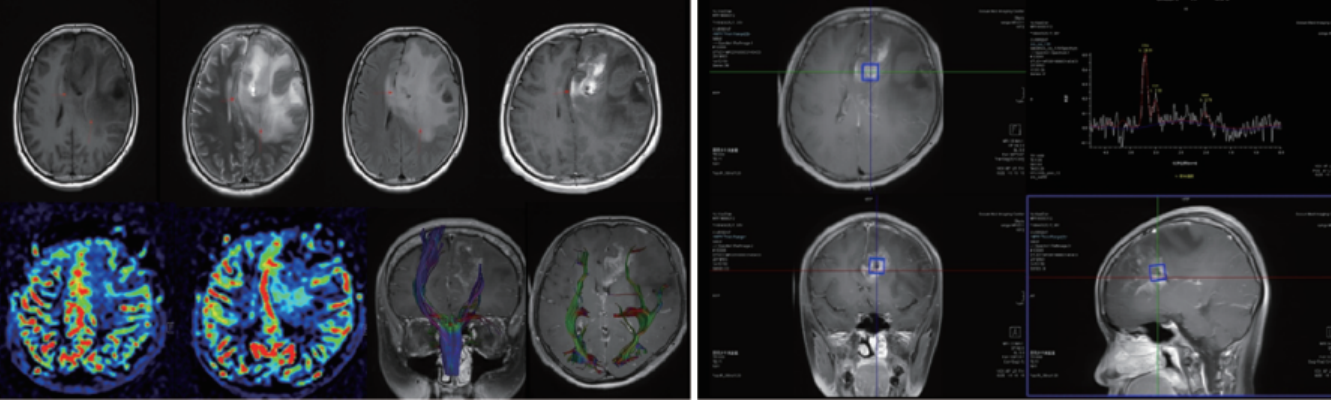

案例圖

腦腫瘤波譜、灌注、DTI